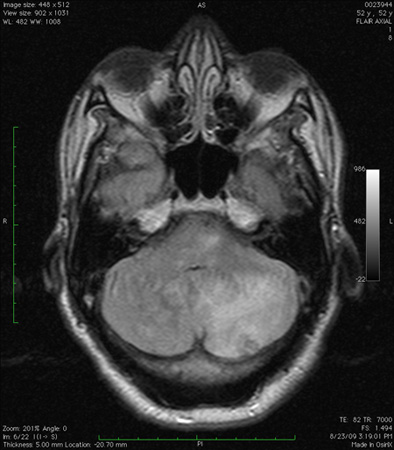

Infarto cerebelar observado através de ressonância nuclear magnética (sequência de recuperação da inversão atenuada por fluidos): observe a presença de edema secundário e a obliteração do quarto ventrículo

Do acervo de Dr. S. H. Subramony; usado com permissão